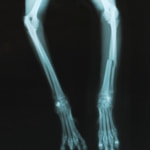

橈尺骨骨折 : 症例1 | 症例2 | 症例3 | 症例4 | 症例5 | 症例6 | 症例7

: 症例8 | 症例9 | 症例10 | 症例11 | 症例12 | 症例13 | 症例14

: 症例15 | 症例16 | 症例17 | 症例18 | 症例19 | 症例20 | 症例21